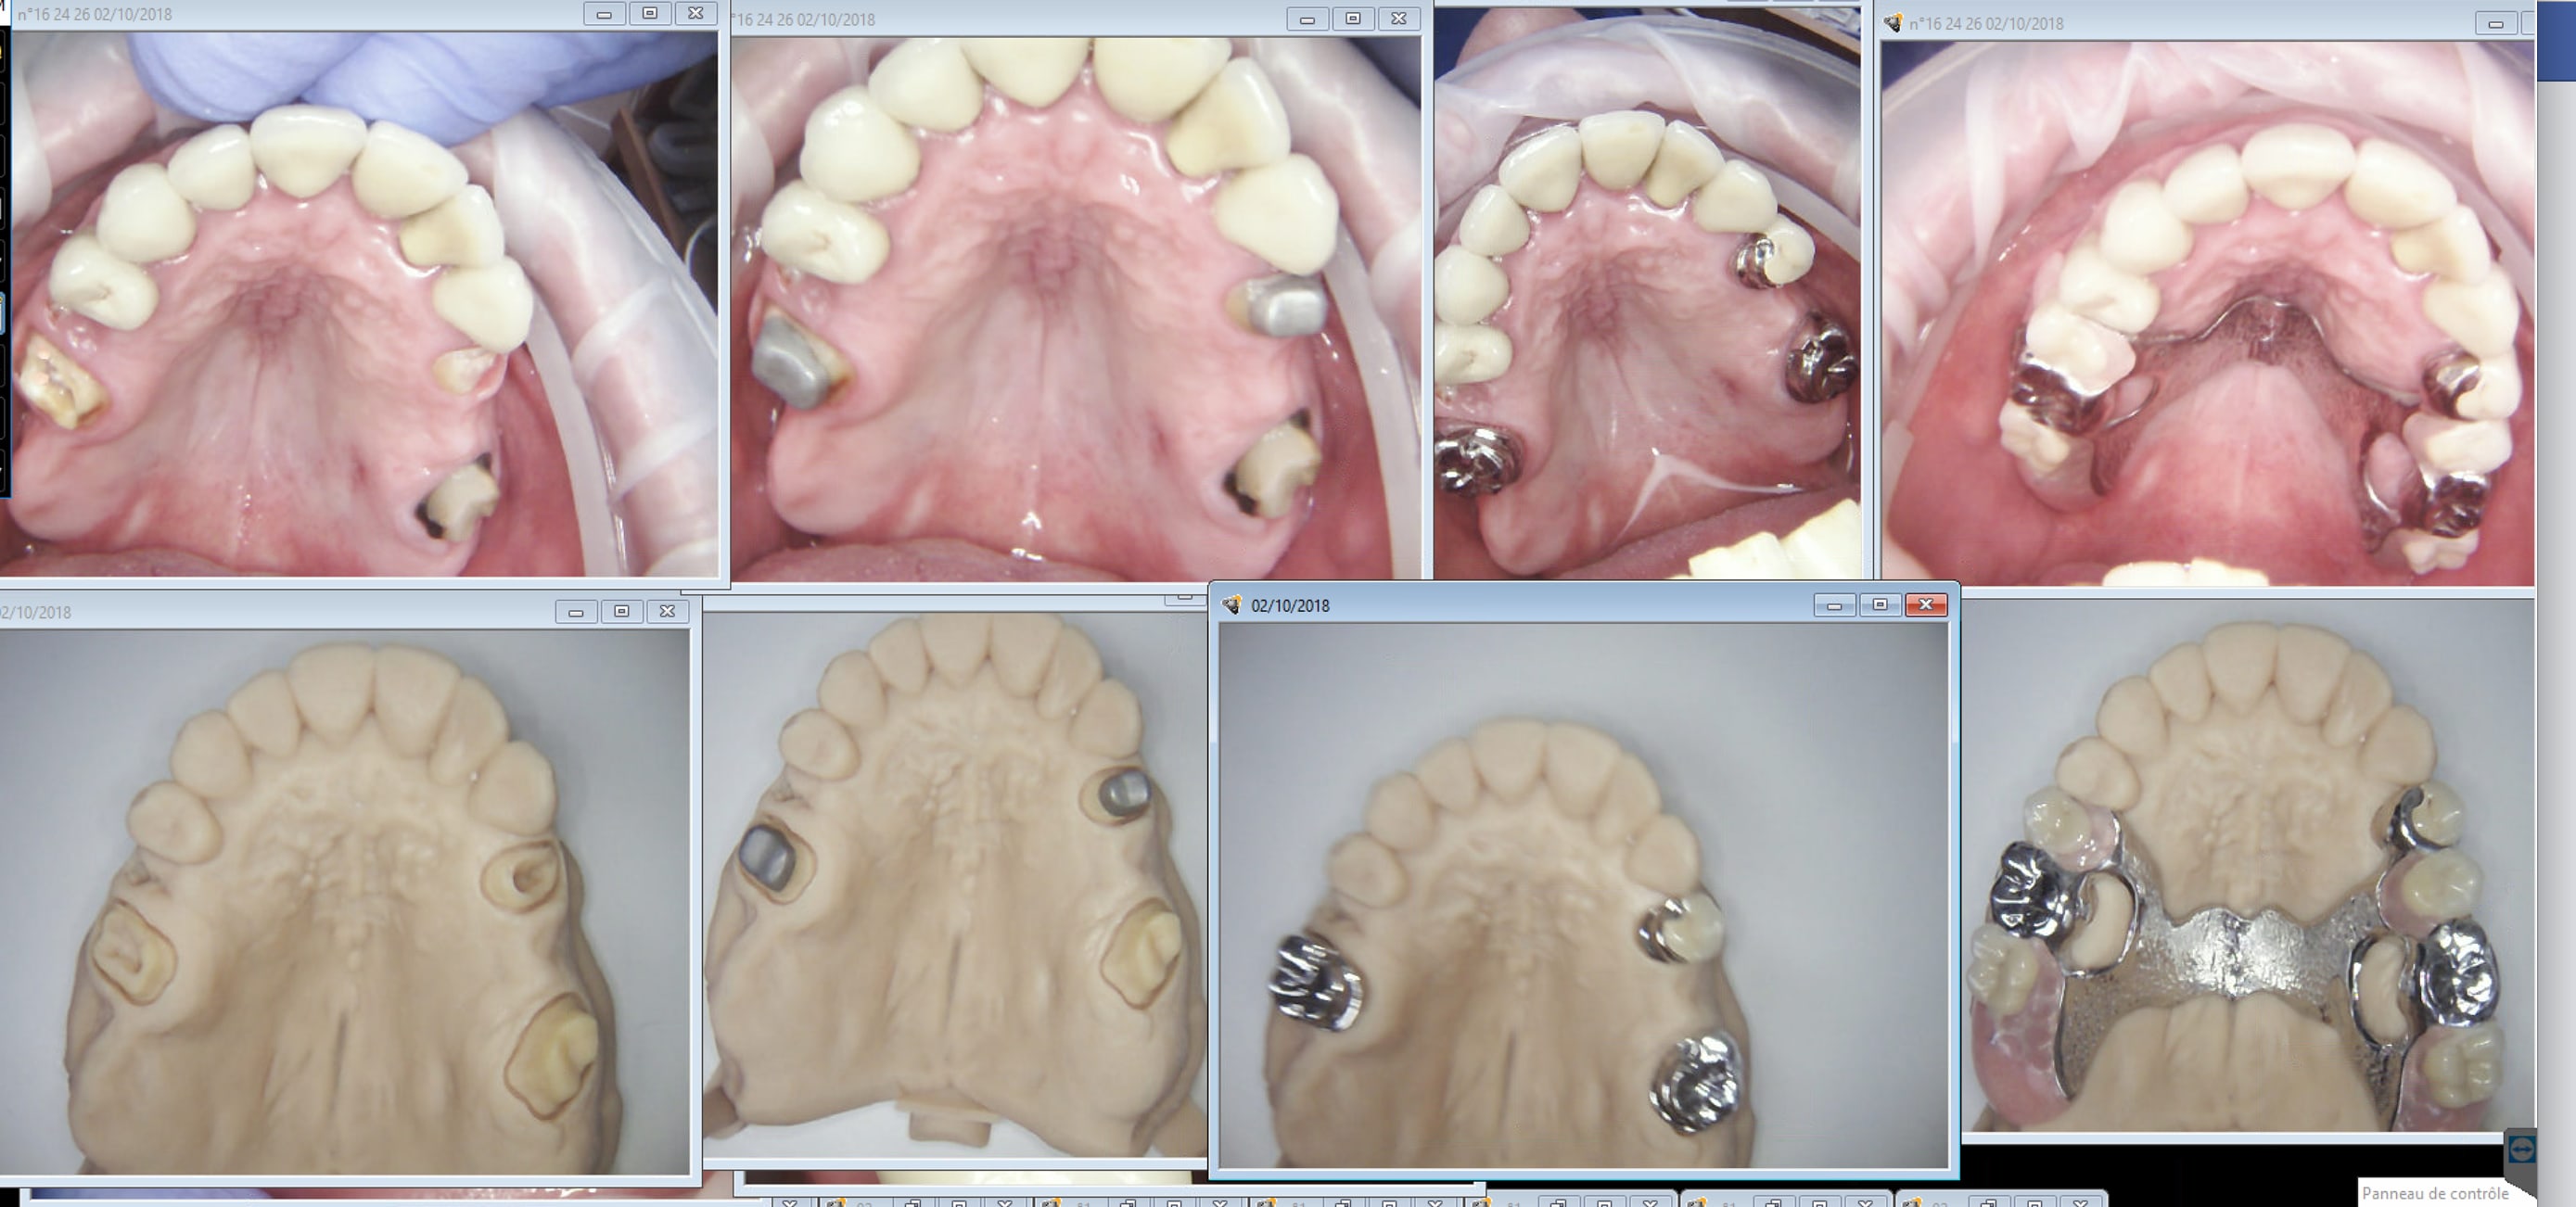

Il y a un avant et un après. IC coiffe stellite one shot.

Le bas aussi. Sans bases d'occlusion une seule empreinte. Finition directe.

Enfin 2. -)))